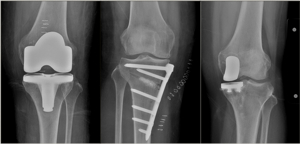

5. 노인 무릎관절 정부지원

관절 수술 지원 사업은 무릎 관절증으로 고통받는 저소득자들의 삶의 질 향상을 위해 노력하고 있으며, 이 사업의 주요 내용은 다음과 같습니다. 지원 대상은 만 60세 이상 건강보험 가입자에게 무릎관절 수술에 대해 최대 120만원까지 실비로 지원됩니다. 세부적인 내용은 아래 블로그 참고하시길 바랍니다.

Q: 무릎 수술 후 회복 기간은 얼마나 걸리나요? A: 개인차가 있지만, 보통 3-6개월 정도 걸립니다. 수술후에는 합병증(혈전,신경손상 등)관리에 주의가 필요합니다.